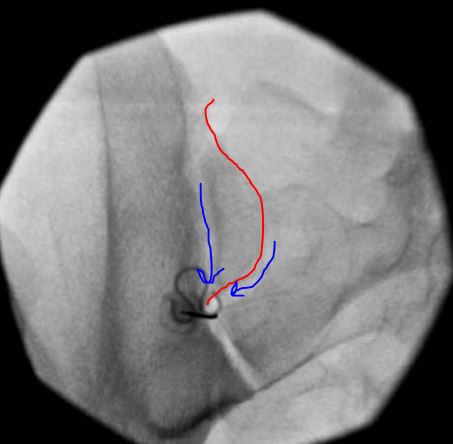

This is on the right side - not a true AP. The fluorscope is tilted caudad (with reference to the detector, not the source) and contra-lateral. The caudad tilt brings the Posterior Superior Iliac Spine (PSIS) to (about) mid joint. Then, rotate contralateral (towards midline) until the two joint lines cross just under the PSIS. This will usually give a flashlight sign - meaning, you get a small square that lights up. This is your spot. It is extremely rare that if you line it up as such, that the needle doesn't slide in the joint.

The red line highlights the PSIS. The blue lines highlight the two joint lines as they cross right below the PSIS.

Caudad tilt (reference to detector) to get the PSIS about mid joint. Then rotate contralateral (so needle will go medial to lateral) until the two lines cross EXACTLY underneath the PSIS. You will see the "box" highlight where the two lines coalecse. In this case the joint lines below this point are overlapping so that appears highlited (bright) as well, but often times, the bright spot is just below the PSIS.

(RED line highlights PSIS. Blue lines highlight the two lines you intersect right below the PSIS).